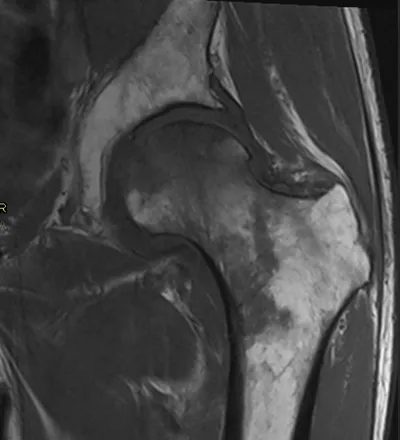

Avascular Necrosis Radiology Images

This collection contains 1 radiology images related to avascular necrosis, including various imaging modalities such as X-rays, MRIs, CT scans, and ultrasound images commonly used in medical diagnosis and education.